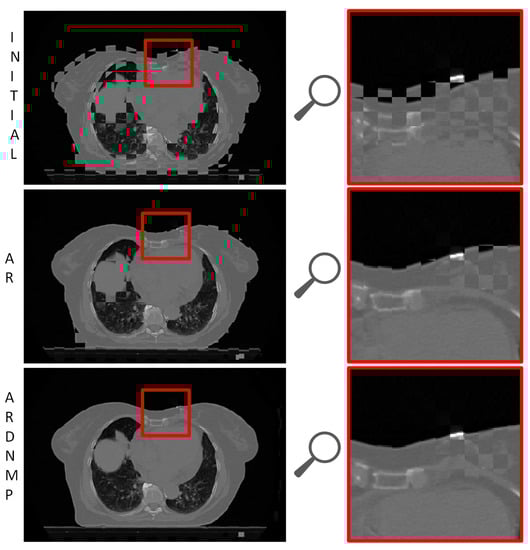

3.3. Visual Assessment